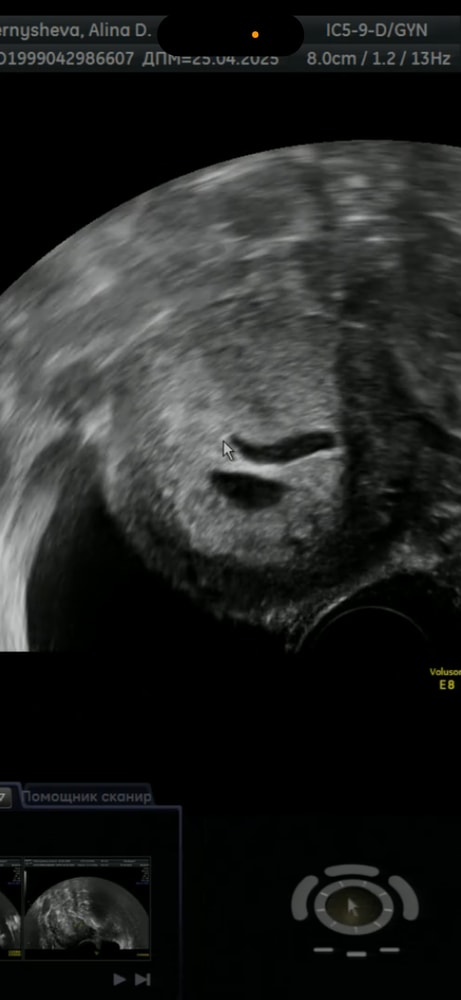

Вчера переделала узи, услышали сердцебиение. Рядом с ПЯ врач увидела полость, сказала, это либо отслойка/гематома, либо второе плодное яйцо, но пустое.

Как вам кажется, что это, гематома, или второе ПЯ?